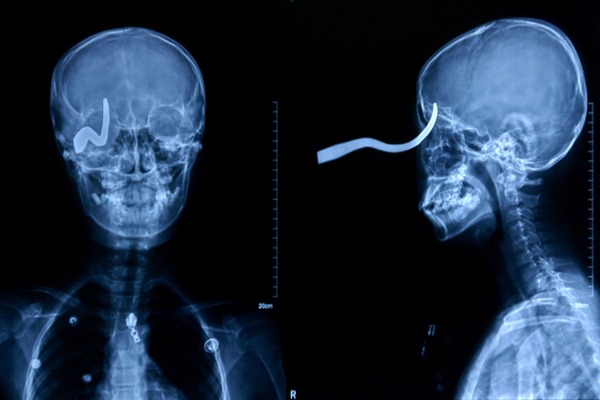

メタリカのスタンド攻撃うけてるやん

脳にダメージなければ意外と無事なのね

メタリカもそうだが、何らかのスタンド攻撃を疑うのも解らんでもないww

以前なんかで聞いた話だけど、米国で頭を鉄棒が貫通して

穴が開いた状態で運び込まれた人が居たそうだ。

その人はその後も生きてたそうだけど、人格が変わってしまったとか。